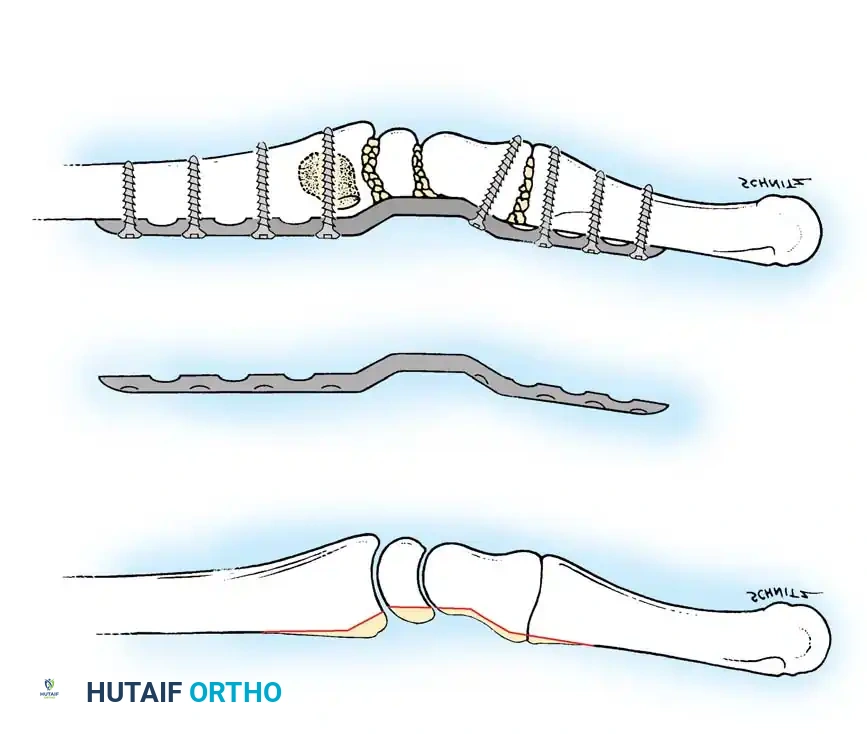

Surgical Technique for Ulnar Shortening Osteotomy:

1. Approach: A longitudinal incision is made over the subcutaneous border of the distal ulna. The interval between the ECU and flexor carpi ulnaris (FCU) is utilized.

2. Plate Application: A specialized ulnar shortening osteotomy plate is applied to the volar or tension surface of the ulna.

3. Osteotomy: A precise oblique or step-cut osteotomy is performed using a cutting guide. The amount of bone resected (typically 2 to 4 mm) is calculated preoperatively based on the degree of positive variance.

Application of a specialized cutting guide to perform a precise, parallel oblique osteotomy of the ulnar diaphysis.

- Compression and Fixation: The osteotomy site is reduced and dynamically compressed using the plate's compression device or an articulated tension device.

The osteotomy is closed and rigidly compressed using a dynamic compression plate, ensuring primary bone healing and immediate structural stability.

- Closure: The periosteum and soft tissues are meticulously closed over the plate to minimize tendon irritation.